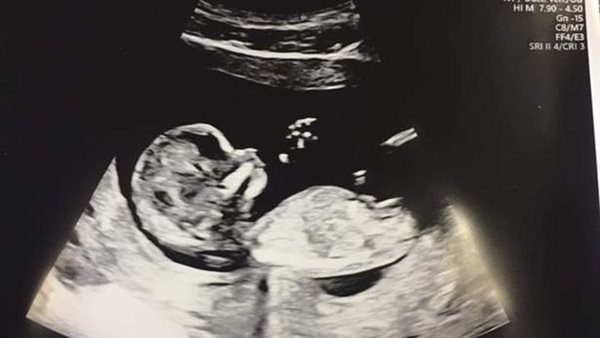

خضع لجراحة بعد ولادته بأسابيع.. اكتشاف إصابة طفل بسرطان نادر فى رحم أمه

16/02/2021 10:44 ص